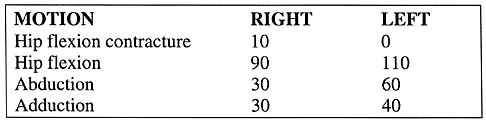

Question 963High Yield

The parents of a previously healthy 3-year-old child report that she refused to walk on awakening. Examination later in the day reveals that the patient can walk but with a noticeable limp. She has a temperature of 99.5 degrees F (37.5 degrees C). Range of motion measurements are shown in Figure 50. An AP pelvis radiograph is normal. Laboratory studies show a WBC count of 9,000/mm3 and an erythrocyte sedimentation rate of 10 mm/h. Management should consist of

Explanation

The patient has the typical history and presentation of transient synovitis of the hip, a condition that is more common in children age 2 to 5 years but which may affect children up to 12 years. The discomfort typically is noted on awakening, and the child will refuse to walk. Later in the day, the pain commonly improves and the child can walk but will have a limp. Mild to moderate restriction of hip abduction is the most sensitive range-of-motion restriction. The extent of the evaluation for transient synovitis depends on the intensity and duration of symptoms. Because she has been afebrile for the past 24 hours, observation is the management of choice. In the differential diagnosis of suspected transient synovitis, septic arthritis of the hip is the primary disorder to exclude. Osteomyelitis of the proximal femur also should be considered. In most patients, clinical examination will differentiate of these disorders to a reasonable certainty. Plain radiographs are normal in the early stage of an infectious process. Ultrasonography shows increased fluid in the hip joint in both transient synovitis and septic arthritis. MRI can differentiate the two conditions; however, this test would require general anesthesia and is not required in most patients in this age group. If a child with transient synovitis has a concurrent infectious process such as an upper respiratory tract infection or otitis media, the temperature will most likely be elevated. In this situation, a full evaluation for an infectious process and initiation of IV antibiotics should be considered. This would include radiographs, CBC count, erythrocyte sedimentation rate, blood cultures, aspiration of the hip joint, and IV antibiotics. Del Beccaro MA, Champoux AN, Bockers T, Mendelman PM: Septic arthritis versus transient synovitis of the hip: The value of screening laboratory tests. Annals Emerg Med 1992;21:1418-1422.